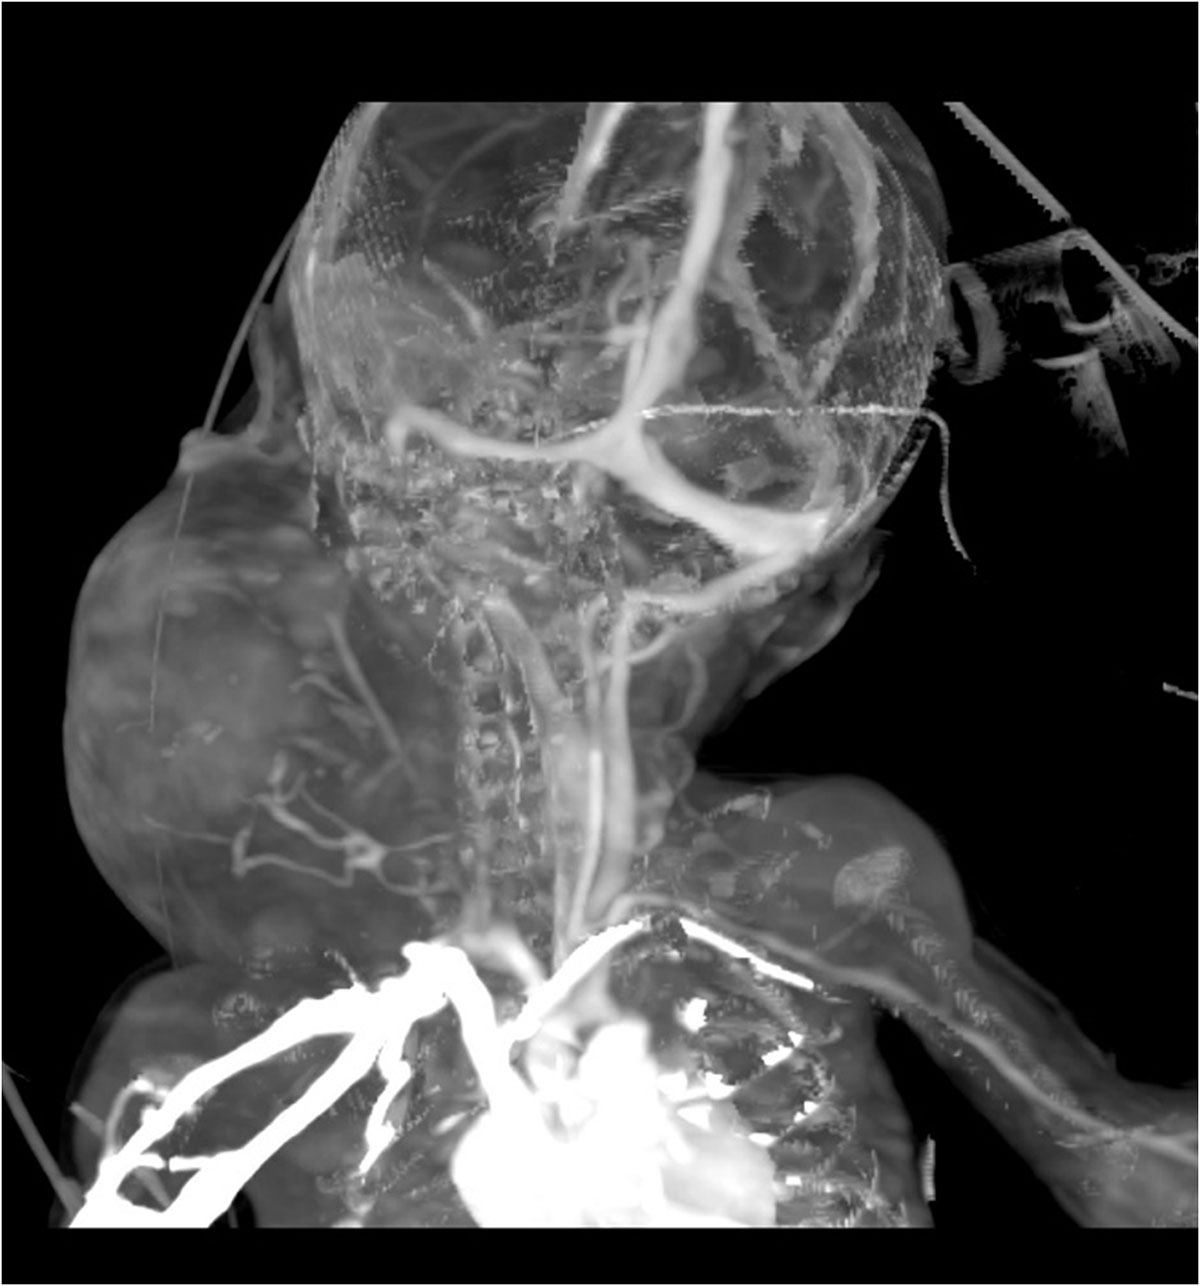

Se identifica imagen redondeada, de bordes lobulados, dependiente de tejidos blandos, heterogénea por áreas sólidas y quísticas internas, así como algunas calcificaciones irregulares dispersas, tras la aplicación de medio de contraste con realce ávido heterogéneo en sus porciones sólidas, con dimensiones de 89.3×88.3×80.9 mm y volumen de 333.6 cc; localizada en los espacios masticador, parotídeo, parafaríngeo, submandibular, visceral, supraesternal, perivertebral bucal y cervical posterior derechos.5. IMÁGENES

¿De qué vaso es el principal aporte vascular de la lesión?

La tomografía computarizada (TC) muestra una masa compleja bien delimitada, con componentes sólidos, quísticos, calcificados y grasos, hallazgo característico de los teratomas maduros. La TC permite valorar la relación con estructuras vasculares, la vía aérea y el mediastino, siendo útil en la planificación quirúrgica.

El tratamiento consiste en la resección quirúrgica completa, la cual puede requerir abordajes multidisciplinarios, especialmente cuando existe compromiso de la vía aérea. En casos diagnosticados prenatalmente, se recomienda la planificación del parto mediante la técnica EXIT (Ex UteroIntrapartumTreatment), que permite asegurar la ventilación del recién nacido antes de cortar el cordón umbilical [1,3].